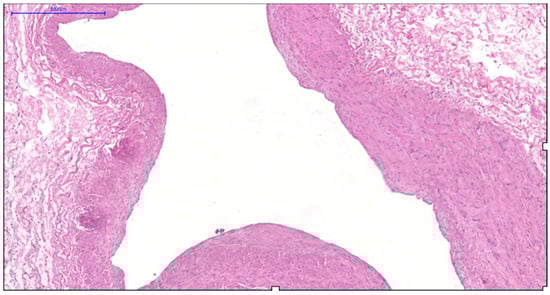

Age-related involution produces alternating zones of tightly packed and sparsely distributed smooth muscle cells within the circular layer, highlighting its structural inconsistency (Figure 7).

Figure 7. Fragment of the great saphenous vein in individuals of the fourth age group. Hematoxylin and eosin staining. Magnification × 100. Disorganization of the longitudinal and circular layers of smooth muscle cells of the middle layer.

Elderly varicose veins contain extensive fibrous regions housing atrophic, randomly oriented muscle bundles, indicative of sclerotic progression (Figure 8). Most myocytes are “dark” cells with elongated cytoplasmic processes; residual “light” cells contain pale mitochondrial matrices and focal cytoplasmic lysis (Figure 9), confirming progressive degenerative changes.

Figure 8. Fragment of the great saphenous vein in a patient from the fourth age group. Hematoxylin and eosin staining. Magnification × 200. The thickness of the inner layer is minimal, while the middle layer is thickened.